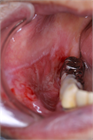

1. 口腔の粘膜疾患は口腔粘膜に症状を呈する病変の総称であり、その中にはさまざまな病変が含まれる。口腔粘膜に限局した疾患、顎顔面領域における病変が波及して口腔粘膜症状を呈したり、自己免疫疾患、内科疾患、皮膚疾患の部分症状が口腔粘膜に出現することもある。口腔粘膜に発現した疾患の鑑別診断により、全身性疾患が発見されることを加筆した。

1. 口腔の粘膜疾患は口腔粘膜に症状を呈する病変の総称である。

1. 口腔の粘膜疾患は口腔粘膜に限局して発現する病変のほかに、内科疾患、自己免疫疾患、皮膚疾患などの部分症状として口腔粘膜に病変が出現するものがある。